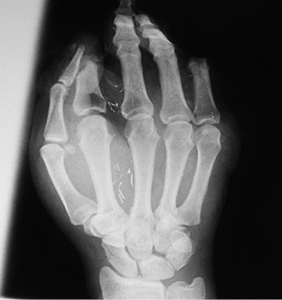

13 pav.

14 pav.

15 pav.

Atokieji rezultatai, praėjus maždaug 13 m. po rekonstrukcinių operacijų. Pacientės taip pat paprašyta parodyti, kaip sugeba suimti rašiklį. Nufotografuota donorinė dešinės pėdos vieta (13–15 pav.)